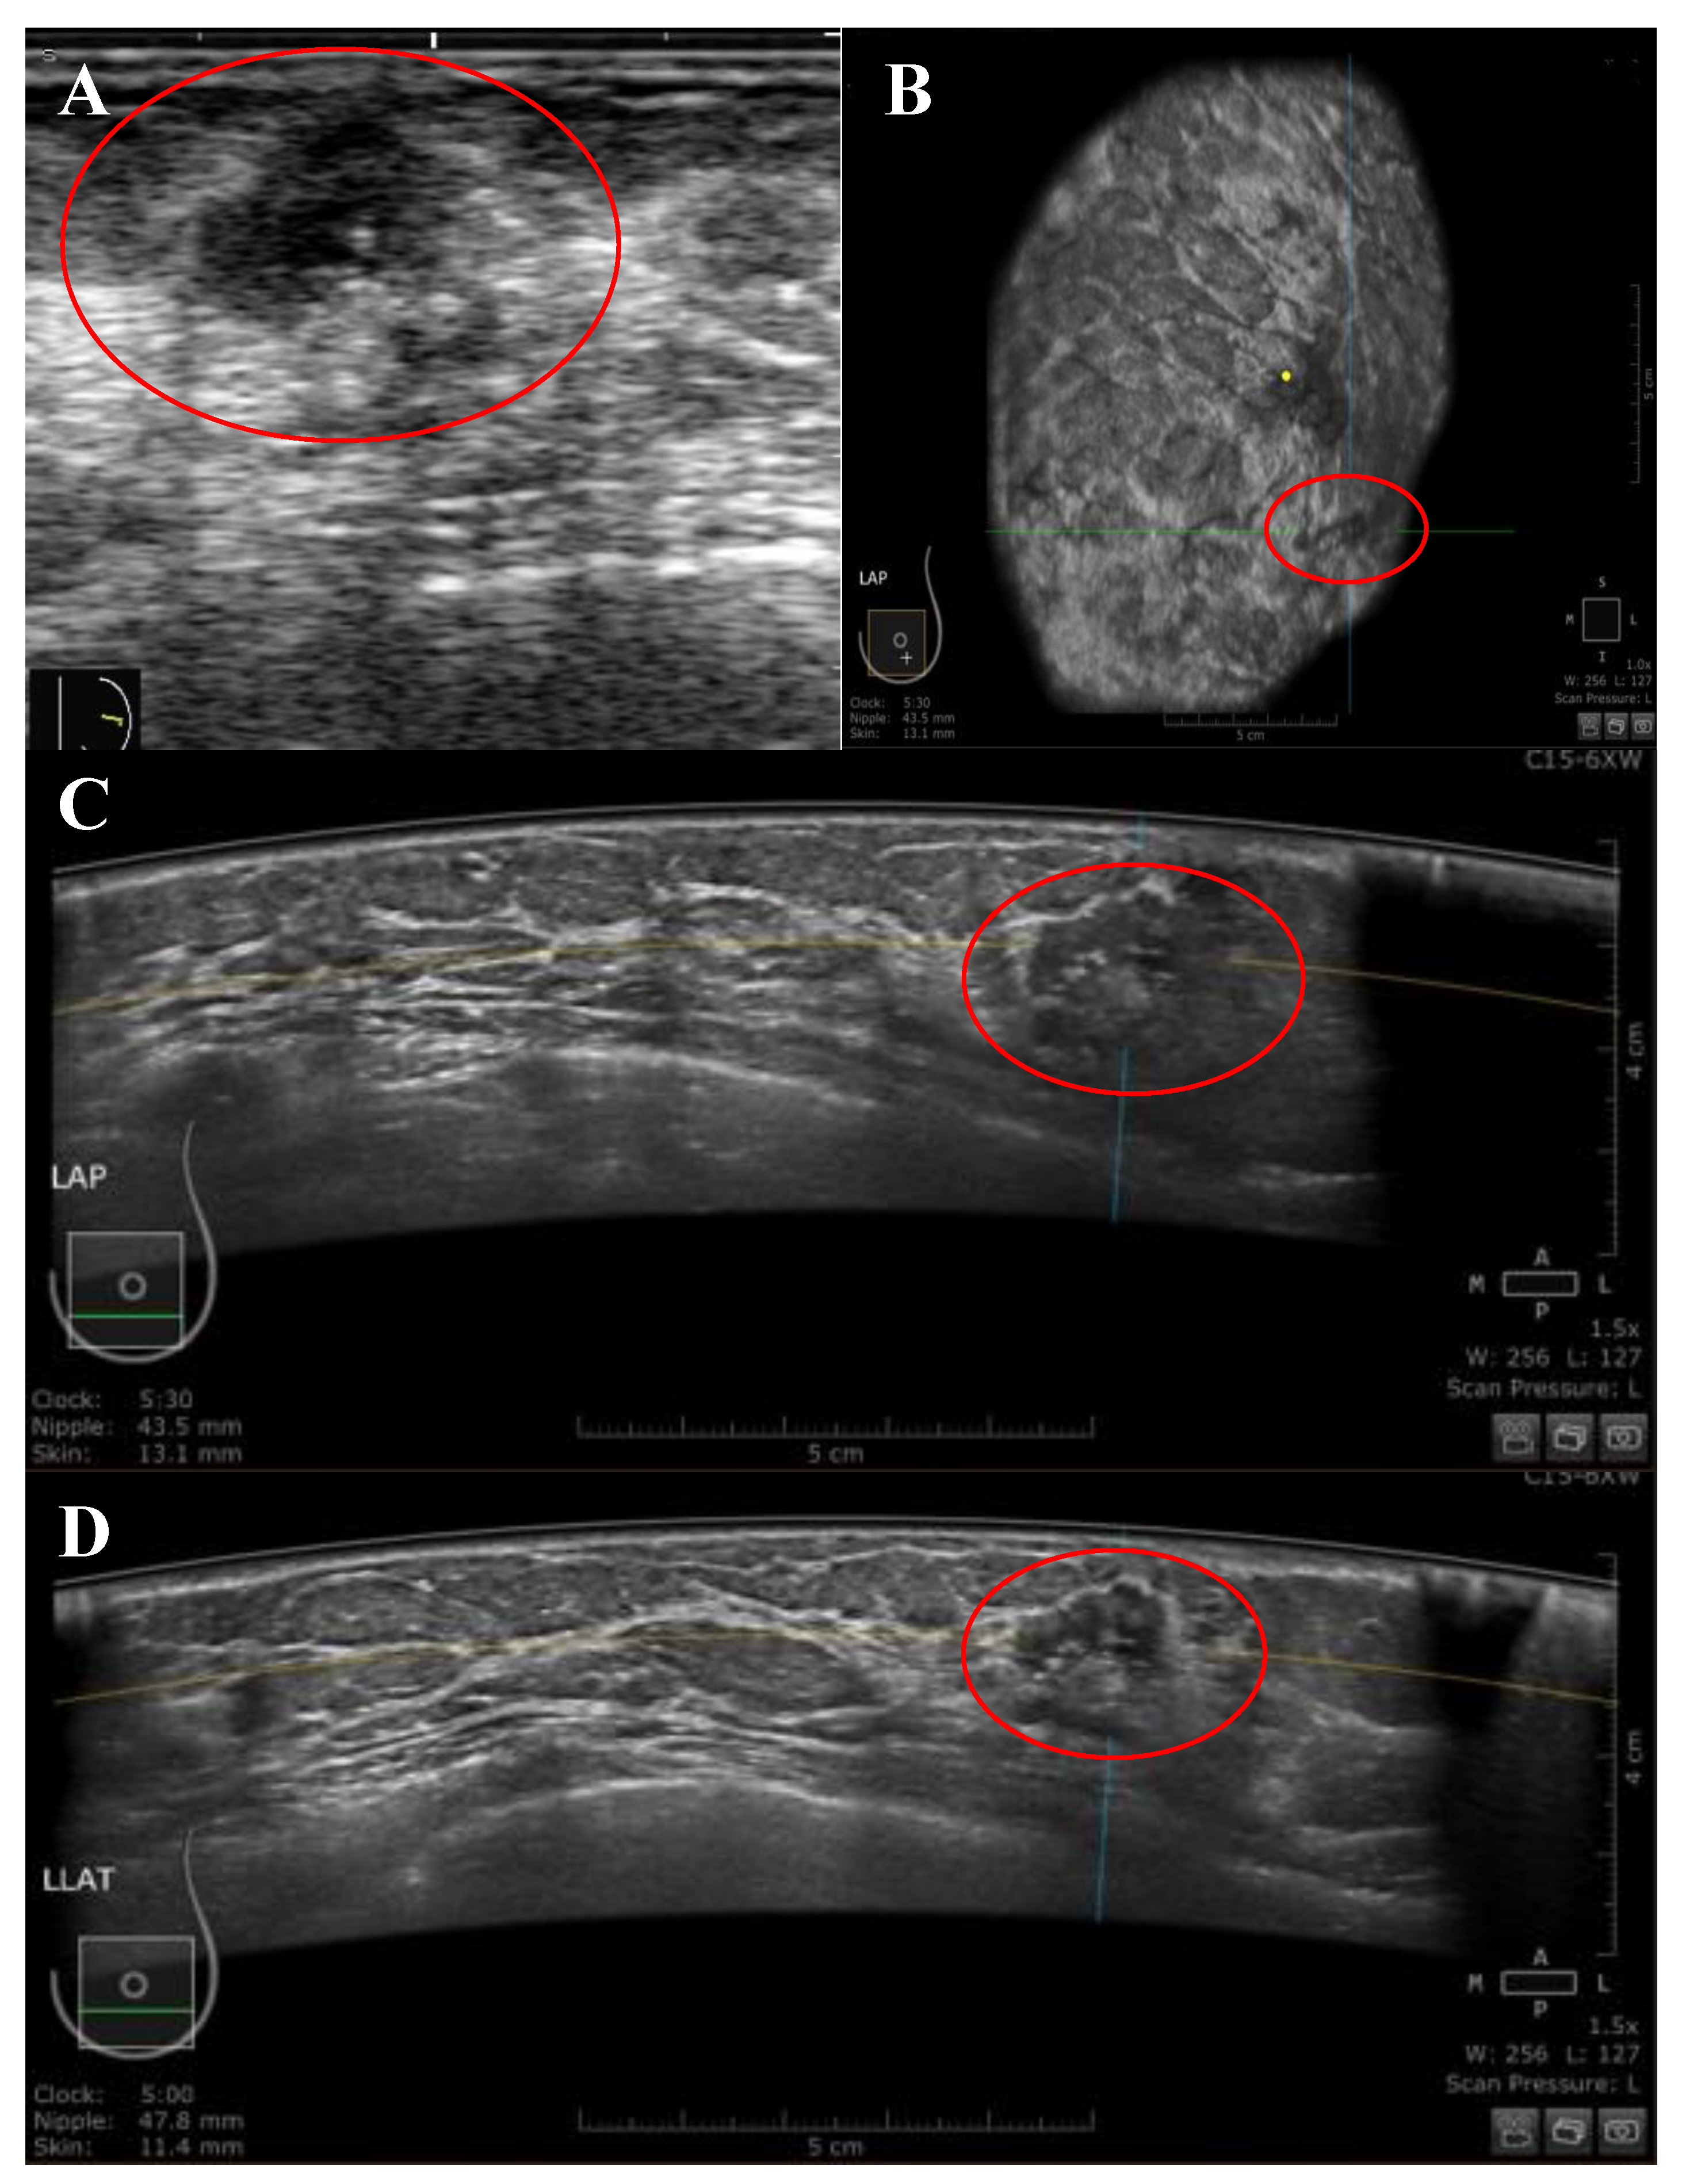

Figure 2.

A 51-year-old Malay female patient presented with a left LOQ breast lump at a distance of 43.5 mm from the nipple. (A) Handheld US image showing irregular-shaped, hypoechoic, non-parallel mass, and heterogenous echo pattern with spiculated margins and acoustic shadowing also showed diffuse inside and outside mass calcifications. The mass was classified as BIRADS category 4 by HHUS. (B–D) the mass was presented by ABUS in three orthogonal planes: coronal (B), transverse (C), and sagittal (D). The mass was classified as BIRADS category 4 by ABUS. The histological evidence indicated a malignant lesion. The yellow dot marks the position of the nipple, and the red circle marks the lesion.